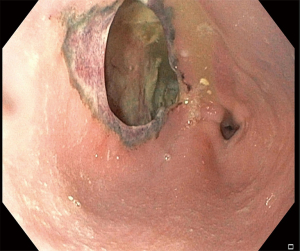

A 38-year-old man without apparent psychiatric/neurologic comorbidities was referred to our hospital 36 hours after the acute onset of dysphagia, drooling and worsening thoracic pain after ingestion of a microwave-heated novel potato. The chest X-ray showed evidence of pneumomediastinum. A chest computed tomography (CT) confirmed the presence of pneumomediastinum, left hydropneumothorax and soluble contrast extravasation (Figure 1). The upper endoscopy showed a 4 cm × 2 cm esophageal full-thickness parietal loss located at 30 cm from the incisors. The mucosal edges of the perforation were scarred and inflamed as occurs in thermal injuries (Figure 2 and Video 1). On arrival, the patient was febrile (38.6 ℃), tachycardic (116 bpm), and tachypneic, with normal blood pressure (130/85 mmHg). The physical examination did not reveal subcutaneous emphysema. White blood cell count (18,500/mm3), C-reactive protein (38 mg/dL), procalcitonin (2.35 ng/mL), and lactate (1.98 mmol/L) were altered. The patient underwent hybrid esophagectomy via laparoscopy and right thoracotomy with gastric conduit reconstruction. A circular stapled 25 mm anastomosis was fashioned at the apex of the thorax and a pleural patch was used to reinforce the suture. Both the right and left chest were drained and a feeding jejunostomy was performed for nutritional support. The postoperative course was uneventful. An upper endoscopy performed on postoperative day (POD) 5 showed regular anastomosis. The patient was discharged home on POD 9 on a soft diet. The histological examination of the specimen did not reveal peculiar alterations. At 8-month follow-up, the patient was doing well with a well-tolerated regular diet. The upper endoscopy showed normal anastomosis and gastric conduit. All procedures performed in this study were in accordance with the ethical standards of the institutional and/or national research committee(s) and with the Helsinki Declaration (as revised in 2013). Publication of this case report and accompanying images was waived from patient consent according to the institutional ethics board of IRCCS Ospedale Galeazzi - Sant’Ambrogio (No. #2023-OGSA1452).

Acute thermal injuries to the esophagus are uncommon causes of esophageal injury (11). Various degrees of esophageal injury have been reported depending on the temperature, amount of ingested food, physical state (i.e., liquid or solid), and exposure time (12). Linear erythema with white pseudomembranes has been described after ingestion of hot beverages (candy-cane esophagus) (11). These injuries are usually superficial and self-limiting. Similarly, hot solid foods may cause mucosal thermal injury (12,13). The damage pattern is heterogeneous with superficial ulceration, linear erythema, and submucosal blister while no perforations have been described until now. To the best of our knowledge, this is the first reported case of full-thickness esophageal perforation after ingestion of a microwave-heated new potato. New potatoes are not a specific variety; any potato that is harvested early in the season is called new. Other than the small size, a characteristic of new potato is that they keep their shape and consistency once oven or microwave cooked. Differently from the conventional oven heating that involves heat transfer from outside to inside, microwave heating involves energy conversion from electromagnetic to thermal energy. Microwaves are low-energy electromagnetic waves with a wavelength in the range of 0.001–0.3 meters and a frequency in the range of 1,000–300,000 MHz. During the heating process, electromagnetic waves oscillate within the oven and interact with food particles, leading to heat generation and rise in temperature. Specifically, microwaves cause heating from the inner layers toward the outer layers. This generates an inside-out thermic effect while internal parts are heated faster than those located outside. In the present case, we can assume that the ingested potato was warm outside and hot in the core. The single-swallow ingestion of this potato impacted the thoracic esophagus causing acute onset of dysphagia and drooling. The mechanism of damage may be attributable to the protracted thermal injury with consequent punched-out full-thickness delayed perforation. Because of the significant wall defect with loss of tissue (Figure 2) in conjunction with endoscopic evidence of burned and scarred edges, primary repair was not attempted whereas esophagectomy was preferred (14). Thoracotomy was preferred over a minimally invasive approach to obtain a better exposure of the middle third of the esophagus and faster infectious source control. Because of the limited right pleural space contamination, the anastomosis was located at the apex of the thorax and reinforced with a mediastinal pleural patch to possibly reduce the risk of leak (15,16).